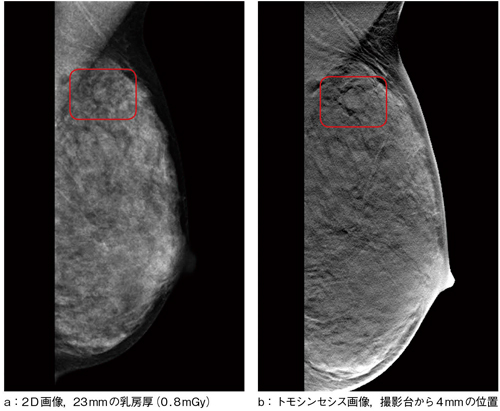

図2 2D画像とトモシンセシス画像の比較

(画像ご提供:亀田京橋クリニック様)